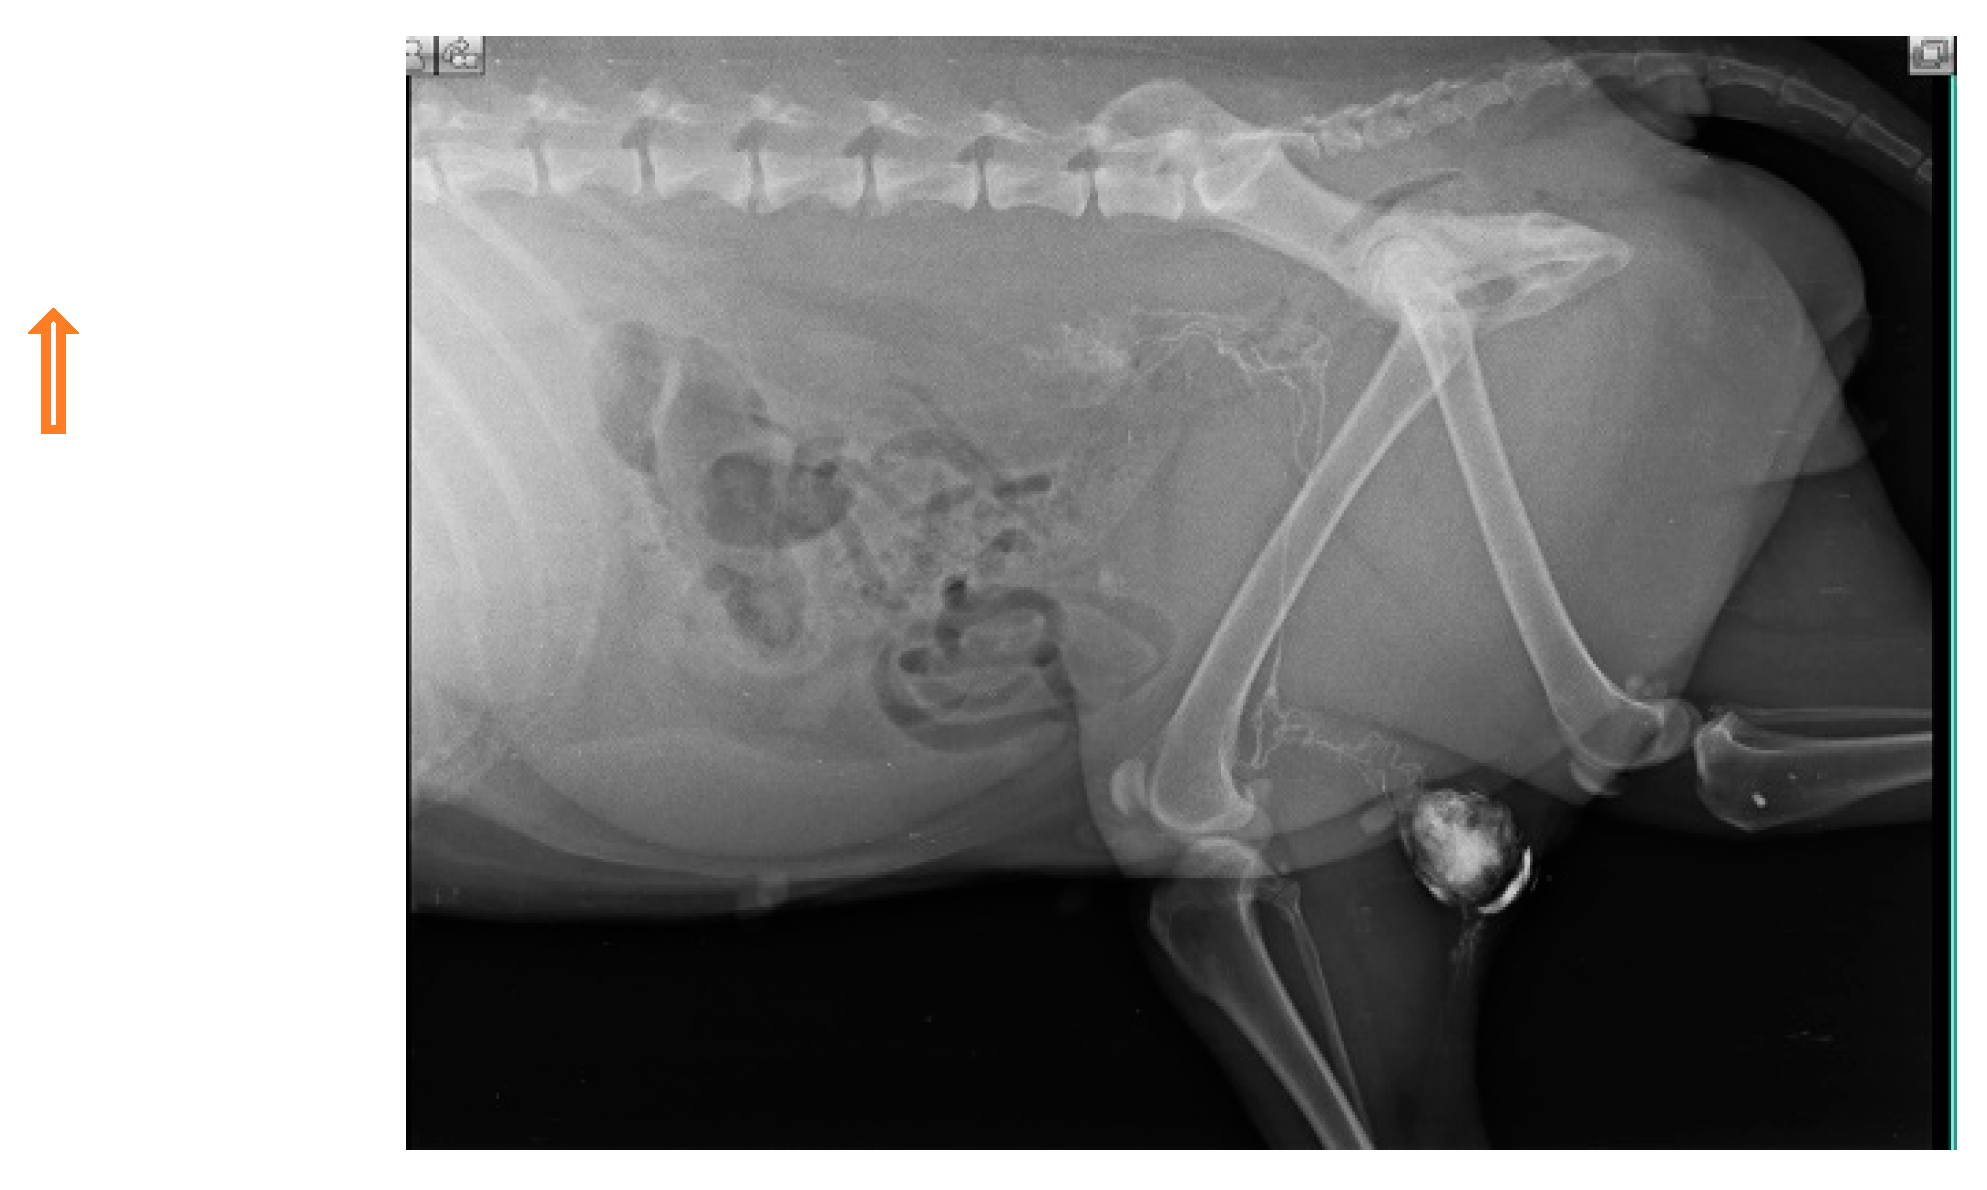

In multicentric lymphosarcoma (n=6), within minutes of peritumoral and intradermal injection of iohexol in popliteal LN, deep inguinal LN and miLN were discovered as SLN as shown in Fig. 9.

Figure 9. Lymphatic channel from popliteal lymph node to inguinal lymph node and then to medial iliac lymph node (solid white arrow) in multicentric lymphosarcoma.

Preprints 77141 g009

The malignancy criteria of the peripheral LN (submandibular, parotid, cervical, axillary, inguinal, and popliteal LN) were clearly described by ultrasonography. These criteria include oval form with S/L ratio 1, peripheral and central vascularization, and hypoechoic nodes as shown in Fig. 10, which are confirmed by cytology and biopsy. In the case of a primary tumor mass (lymphoma at 3rd molar) in the mouth cavity, mandibular LN were recognized as SLN within 2 minutes of indirect CT lymphography with iohexol. All superficial LN were found to have metastasized in lymphosarcoma which was a poor predictor of survival time.

Figure 10. Malignant changes observed through B-mode USG and color Doppler as generalized lymphedema (hypoechoic texture with S/L ratio ≤ 1, peripheral and central vascularization) in lymphosarcoma (ocular form).

Preprints 77141 g010